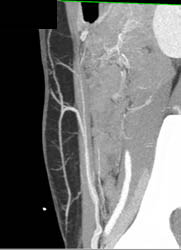

DIEP Flap Planning